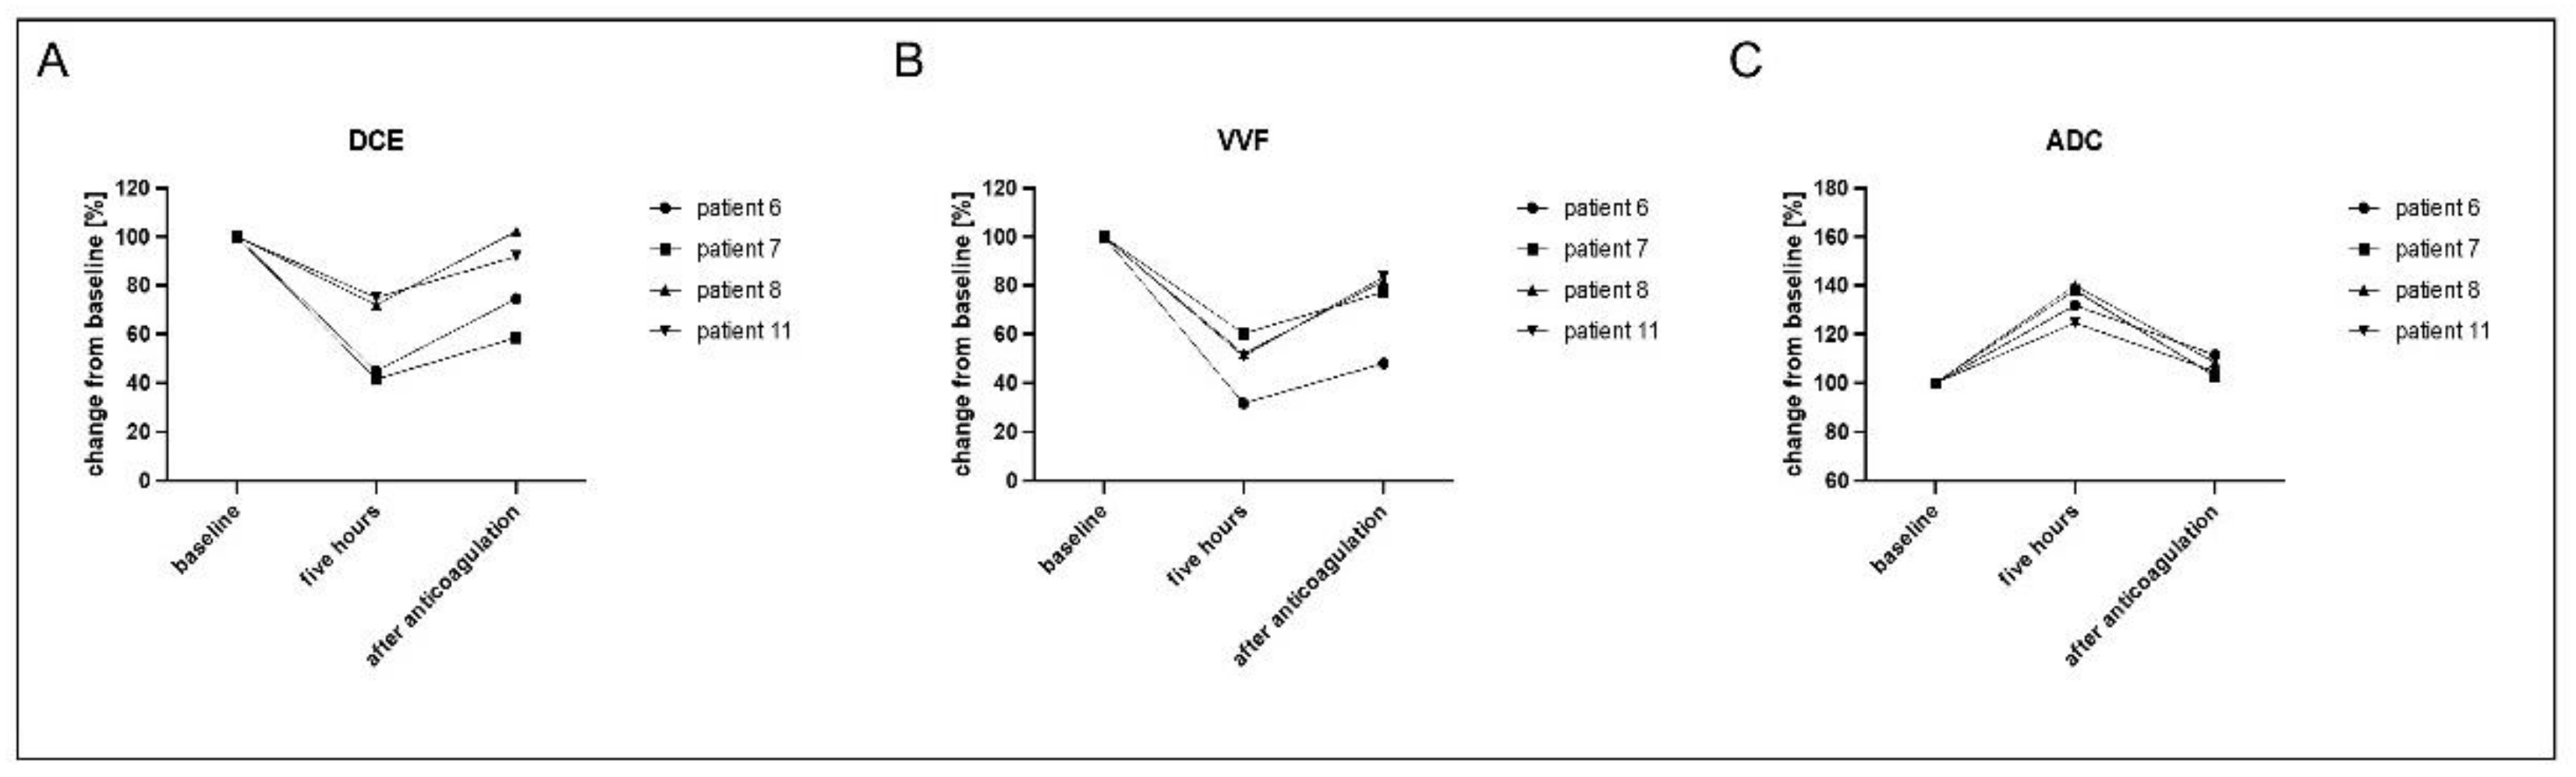

3.3. Evaluation of Reversed Effects Due to Therapeutic Anticoagulation